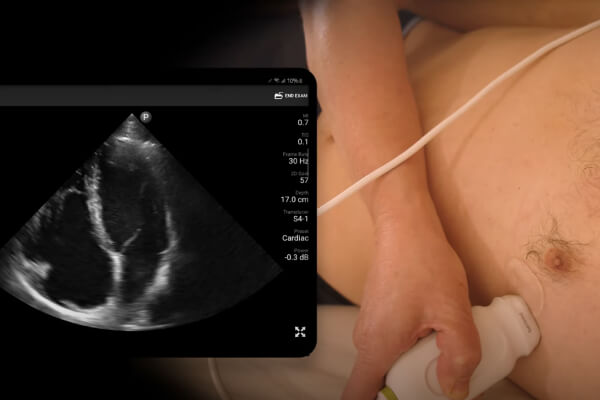

PLAX View

Learn how to obtain the parasternal long axis